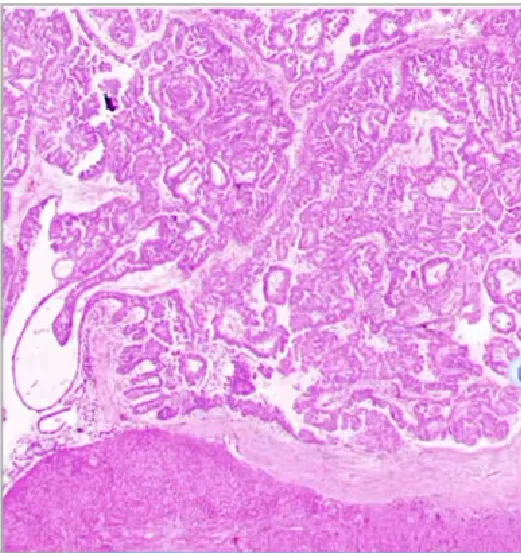

淋巴腺复合体样腺癌(Lymphoglandular complex-like adenocarcinoma)

• 罕见,也被称为穹顶癌(dome carcinoma)或gut-associated lymphoid tissue carcinoma;

• 其特征是伴有明显的淋巴组织

• 其组织学表现让人联想到淋巴腺复合体,腺体排列紊乱、促结缔组织增生、坏死和/或单个细胞,提示恶性;

• 大多数病例局限于黏膜下层或更深浸润;

• 相关分子数据较少,部分显示微卫星不稳定(MSI);

• 可能会发生淋巴结转移,但总体预后良好